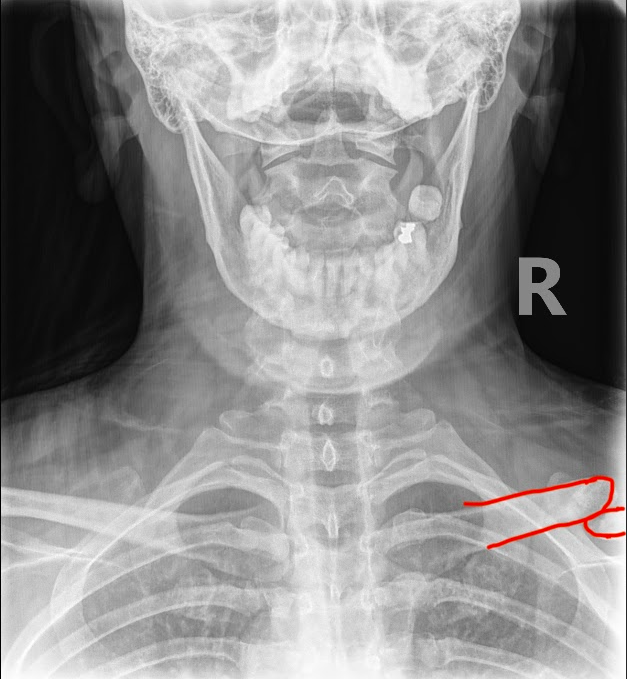

DACBRs Diagnose a Chronic Clavicle Fracture

DACBRs Diagnose a Chronic Clavicle Fracture Fig. 1 AP cervical view Fig. 2 AP cervical view showing red annotation highlights